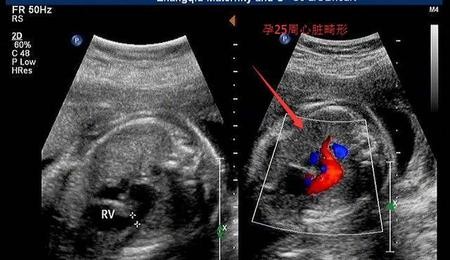

其中到第七周时,胚胎长到1.3cm,手臂和腿开始生出,连手指都开始会分化出;而内部器官如心脏也会分出左右心房。

第八周胎儿定型,头、身体、四肢都已分化完成,胎囊占到宫腔一半,心脏也开始搏动。

在平安度过孕早期后,要按时做好每次产检,尤其是染色体排畸检查(早唐、nt筛查、唐筛),四维检查等排畸检查。